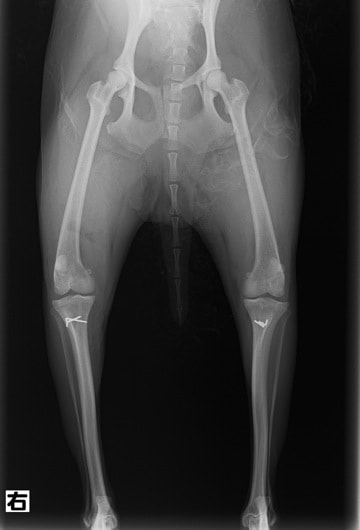

■ 症例24 キャバリア 7か月

左右膝蓋骨内方脱臼(左:グレードⅣ 右:グレードⅢ)

以前から左右後肢の跛行が認められ、整形外科学的検査・レントゲン検査により左右の膝蓋骨脱臼が認められた。症状が重度である左膝の膝蓋骨脱臼整復術を行った。外科手技は縫工筋及び内側広筋の解放、脛骨粗面の外側転位、滑車ブロック形造溝術、内外側関節方の縫縮を実施した。術後一か月時点で、左の膝蓋骨は安定しており経過は良好である。

本症例は成長期における重度の膝蓋骨脱臼であり、術後の再発の可能性もあるため、経過をしっかりと観察していく必要がある。また、今回手術を実施していない右膝に関しても経過を観察し、手術を検討していくこととする。